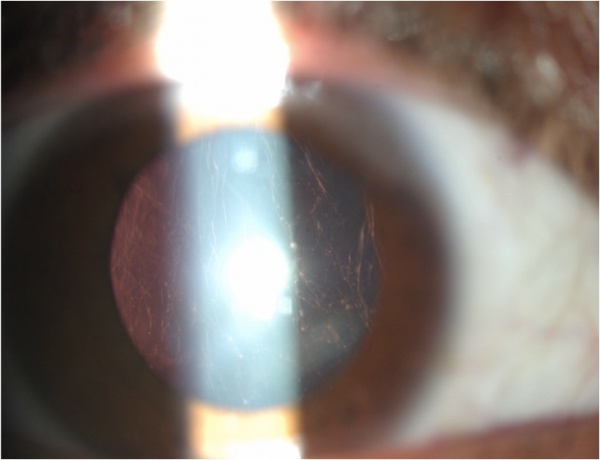

The most common ocular findings in Stickler syndrome are vitreous syneresis in a membranous or beaded configuration and radial perivascular retinal lattice degeneration, both of which are present in up to 100% of affected patients[6]. These vitreoretinal abnormalities may lead to a giant retinal tear and rhegmatogenous retinal detachment in up to 50% of patients. Other findings include axial myopia (present in 80%) resulting from megalophthalmos, open-angle glaucoma resulting from anterior segment dysgenesis,[7][8] and cataract. The cataract is typically a congenital quadrantic lamellar opacity, which may not involve the visual axis.

As noted above, the typical cataract found in Stickler syndrome is of a congenital quadratic lamellar type.[2] Such cataracts may or may not negatively impact vision; if decreased vision is present, removal may be performed with standard lensectomy or phacoemulsification. Patients are at an increased risk of both vitreous loss and post-operative retinal detachment; retinal breaks should be addressed prior to cataract surgery.[3]